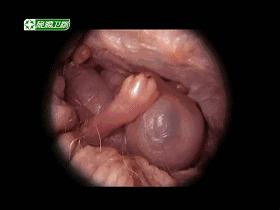

如下图▼怕吓到小朋友,豆豆就不放血腥图片了

《子宫日记》将告诉我们生命最初的美好。 它为子宫开了一扇窗,首度呈现暗无天日的子宫内从未被人得知的世界。记录了不同哺乳动物孕育胎儿的过程,解开生命之谜,感受生命与科学的魅力。

在子宫深处,一个胚胎踏上了漫漫征程。有史以来,我们第一次透过这样的画面窥探到了动物子宫内的秘密世界。